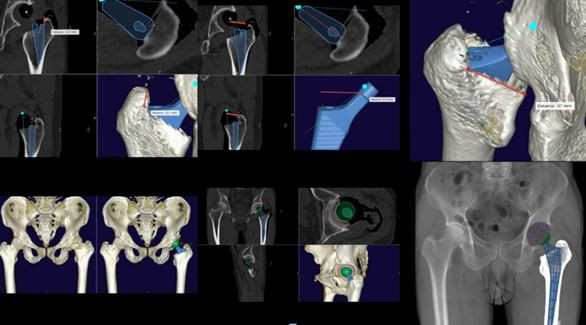

Để lựa chọn loại khớp chính xác, các bác sỹ sẽ sử dụng mô hình 3 chiều xương khớp của chính bệnh nhân làm dữ liệu tính toán độ tương thích.

Sau khi đã lựa chọn được loại khớp nhân tạo thiết kế theo đặc điểm cá thể hóa, các bác sỹ sẽ sử dụng các phần mềm chuyên dụng để lập kế hoạch chi tiết cuộc mổ.

Quá trình này giúp xác định chính xác vị trí cần đặt các cấu phần khớp nhân tạo nhằm tối ưu hóa biên độ vận động của khớp sau mổ, tránh mọi rủi ro cứng khớp hay đi lại tập tễnh. Đồng thời sẽ tiên lượng được một số rủi ro có thể xảy ra xuyên suốt quá trình phẫu thuật.